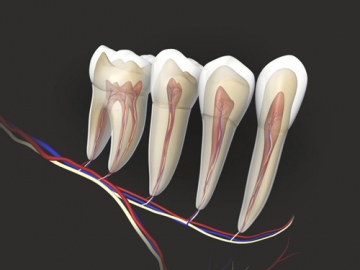

eltávolítása ideg

Miért fogfájás eltávolítása után az ideg. A legvalószínűbb, amikor eltávolítja az ideg hibák történtek:

- anyagot, amely tömítés a fogat, túllépett a gyökér és behatolnak a szövetekbe a fogat körülvevő;

- rosszul előállított töltés gyökérkezelés után az ideg eltávolítása eljárások;

- volt a fertőzés helyén a fog üreg miatt nem teljes eltávolítása a fertőzött szövet és a szegény tisztítási üreg;

- fogászati eszköz letörnek kezelése során, és annak mikroszkopikus rész maradt a fogászati üreg, gyulladást és fájdalmat okozva közben nyomást gyakorol a fogat.

Sok beteg, amelyben megszűnik a idegek a fog üreg történt, úgy vélik, hogy a fog nem éppen fáj, de ez egy félreértés.

Fájdalom akkor is előfordulhat, miután az ideg már eltávolították, és egy kellemetlen érzés, amikor rágás és a nyomás a fogak csak nőni fog.